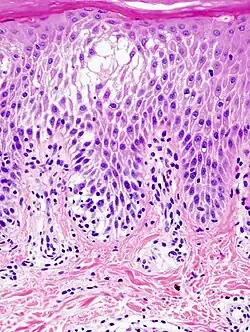

Spongiosis

Spongiosis is mainly intercellular[1] edema (abnormal accumulation of fluid) in the epidermis,[2] and is characteristic of eczematous dermatitis, manifested clinically by intraepidermal vesicles (fluid-containing spaces), "juicy" papules, and/or lichenification.[3] It is a severe case of eczema that affects the epidermis, dermis or subcutaneous skin tissues.[4] The three types of spongiotic dermatitis are acute, subacute and chronic.[4] A dermatologist can diagnose acute spongiotic dermatitis by examining the skin during an office visit, but a biopsy is needed for an accurate diagnosis of the type.